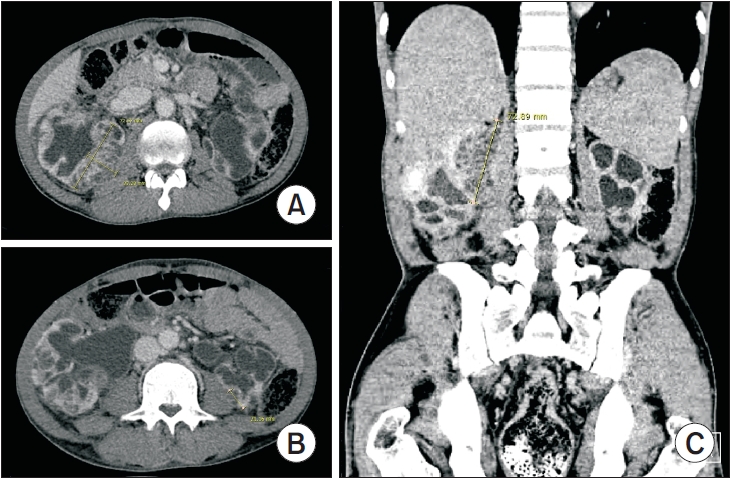

Cyclic Hematuria Misdiagnosed as Hemorrhagic Cystitis in a Rare Case of Vesicouterine Fistula Post-Cesarean Section: A Case Report of Youssef Syndrome

Vesicouterine fistulas are rare complications that may occur following cesarean sections and are frequently misdiagnosed due to their diverse clinical presentations. This report presents a case involving a small vesicouterine fistula initially managed conservatively, which later manifested as cyclic hematuria mimicking hemorrhagic cystitis, ultimately leading to a diagnosis of Youssef syndrome. A 45-year-old woman developed persistent vaginal urinary leakage 3 weeks after a cesarean section. Diagnostic evaluation confirmed a small (<1 cm) vesicouterine fistula. Conservative management with Foley catheterization resulted in spontaneous closure. Four months later, the patient experienced cyclic gross hematuria and dysuria without menstruation, and was subsequently diagnosed with Youssef syndrome. Hormonal therapy using continuous oral contraceptives successfully resolved the hematuria, providing a noninvasive therapeutic option. This case highlights the importance of considering Youssef syndrome in patients with cyclic hematuria after cesarean section, in order to distinguish it from hemorrhagic cystitis and ensure timely, appropriate management.